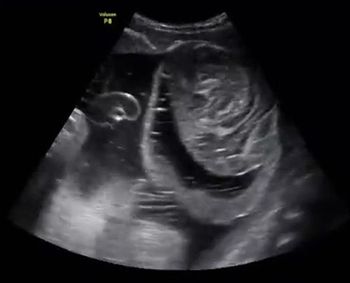

QUIZ: What's causing the compression of the fetal heart (tubular shaped), ascites and dilated trachea?